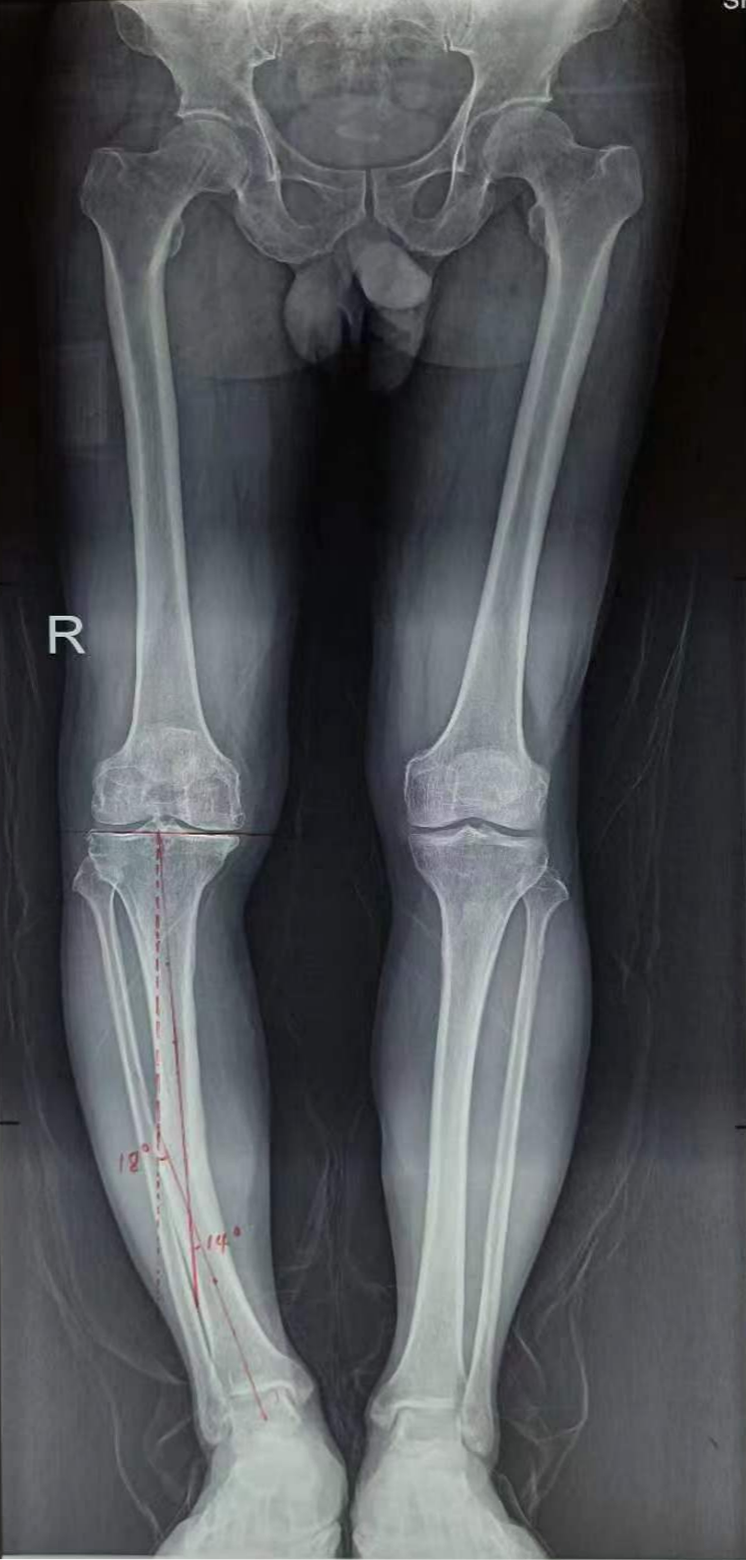

术前

63岁的患者刘大爷,多年前因为一次意外摔伤导致右小腿骨折,当时由于各种条件所限,未行手术治疗,而选择了石膏固定的保守治疗,骨折虽已愈合,但由于对位对线不良导致了骨折畸形愈合,骨折畸形愈合所导致的美观、疼痛等问题不仅给刘大爷生活带来不便,更是造成肉体、精神上的巨大创伤。

不愿继续忍受病痛折磨的刘大爷终于下定决心入院接受手术治疗。入院后,董孟政主任医师针对刘大爷右小腿骨折畸形愈合和因力线改变造成膝关节内侧间室异常磨损的问题,制定详细的治疗方案。对骨折畸形愈合的部分,决定截断骨头,纠正成角恢复力线;对于磨损严重膝关节内侧间室,行膝关节单髁置换;这样既矫正了畸形,又缓解了膝关节疼痛。